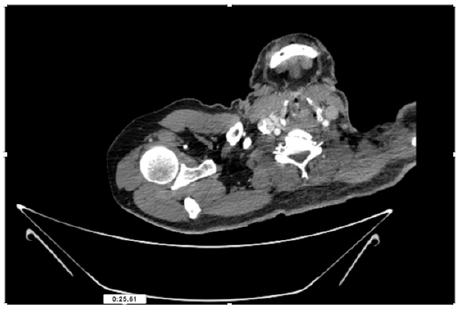

55-years-old chronic smoker had acute, severe pain in the right upper limb for one week; it was cold upto mid arm with skin discoloration. He also noticed numbness and weakness of movement of elbow joint. He underwent below elbow amputation in February 2023 for acute ischemia of left upper limb. He was a current chronic smoker; 15 pack year. General condition was weak; temperature was normal; blood pressure was 100/60mmHg; heart rate was 92/minutes with sinus rhythm; SpO2 was 97% on air; heart was normal. In lower extremities, all peripheral pulses were intact. Local Examination of right upper limb revealed as follows: tenderness; coldness; discoloration; decreased motor function and sensory modalities. Axillary, brachial and radial pulses were not palpable. Hand-held Doppler failed to detect any signal in arterial system; therefore, we arranged for emergency embolectomy. complete occlusion of right upper limb arterial system Full blood count showed high hemoglobin (14.6gm%); normal total WBC and platelet count. Coagulation profile was normal. Parenteral unfractionated heparin, antibiotics, tramadol, proton-pump inhibitors, anti-platelets and HMG CoA reductase inhibitors were given. Doppler ultrasound demonstrated complete occlusion of right upper limb arterial system. CT Angiogram illustrated occlusion of subclavian artery downwards on both sides. Figures 1-14 shows complete occlusion of right subclavian artery without collaterals. On Day ‘2’ of admission, the patient passed black tarry stool for 3 times. However, the vital signs were stable; blood pressure was 100/60mmHg; heart rate was 92/min; SpO2 was 97% on air; the abdomen was soft and not tender. Above elbow amputation was done on Day ‘2’ of admission. Intra-operative findings were as follows: (1) no active bleeding at brachial artery; (2) thrombosis along brachial artery; (3) muscle color and consistency were not healthy.

Figure 10: CT Angiogram at upper arm showing totally occluded right axillary artery; normal internal carotid artery and external carotid artery.